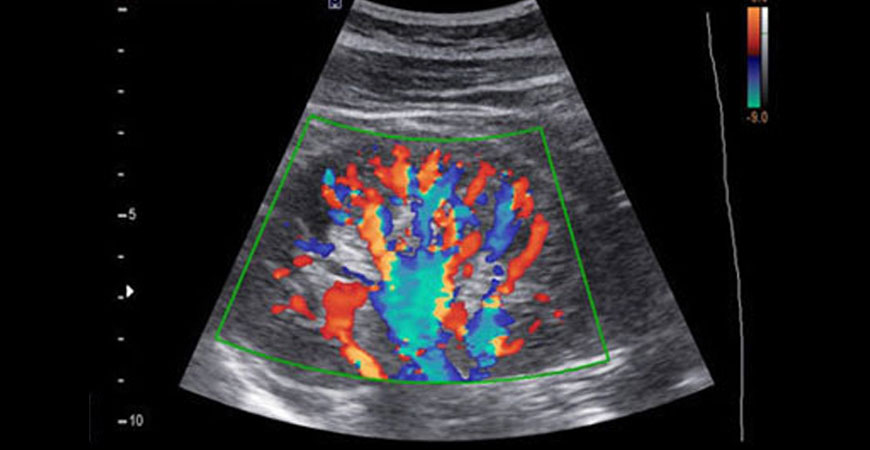

A Doppler ultrasound, also called a Color Doppler test is a non-invasive test that can be used to estimate your blood flow through blood vessels. Our doctors at Aayush Hospital evaluate blood flow through major arteries and veins, such as those of the arms, legs, and neck. It can show blocked or reduced flow of blood through narrow areas in the major arteries of the neck that could cause a stroke.

Color Doppler